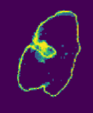

Despite the state-of-the-art performance for medical image segmentation, deep convolutional neural networks (CNNs) have rarely provided uncertainty estimations regarding their segmentation outputs, e.g., model (epistemic) and image-based (aleatoric) uncertainties. In this work, we analyze these different types of uncertainties for CNN-based 2D and 3D medical image segmentation tasks. We additionally propose a test-time augmentation-based aleatoric uncertainty to analyze the effect of different transformations of the input image on the segmentation output. Test-time augmentation has been previously used to improve segmentation accuracy, yet not been formulated in a consistent mathematical framework. Hence, we also propose a theoretical formulation of test-time augmentation, where a distribution of the prediction is estimated by Monte Carlo simulation with prior distributions of parameters in an image acquisition model that involves image transformations and noise. We compare and combine our proposed aleatoric uncertainty with model uncertainty. Experiments with segmentation of fetal brains and brain tumors from 2D and 3D Magnetic Resonance Images (MRI) showed that 1) the test-time augmentation-based aleatoric uncertainty provides a better uncertainty estimation than calculating the test-time dropout-based model uncertainty alone and helps to reduce overconfident incorrect predictions, and 2) our test-time augmentation outperforms a single-prediction baseline and dropout-based multiple predictions.